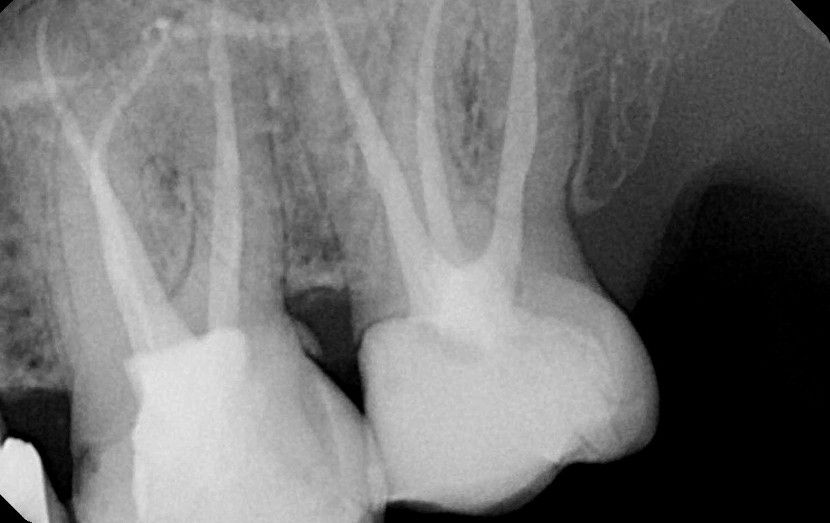

Endodontski zahvati su među najpreciznijim i najsloženijim postupcima u stomatologiji. Cilj endodoncije je uklanjanje inficiranog pulpnog tkiva i bakterijskih ostataka iz kanala, te zatvaranje, tj. punjenje kanala odgovarajućim materijalom. Korijenski kanali su vrlo malih dimenzija , a nepotpuno uklanjanje bakterija iz njih ima posljedice na budućnost i očuvanje zuba.

Moderna stomatologija nam omogućava adekvatan endodontski tretman zuba, a u tome nam pomaže i vrhunska aparatura, te novi sustavi koje primjenjujemo u svojoj ordinaciji.